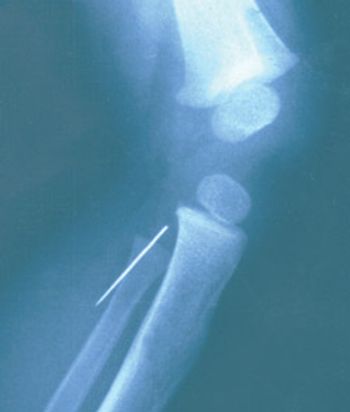

This 33-year-old Guatemalan man presented to a medical mission camp with generalized bilateral knee pain and inability to extend his leg without pain. The 4-ft 11-in patient had mild scoliosis, increased elbow carrying angles, and hypoplastic patellae. He had had dysplasia of the nails with triangular lunulae since birth. The fingernails were absent on the first and second digits of both hands. His mother had had similar physical findings. He had not had regular medical care.